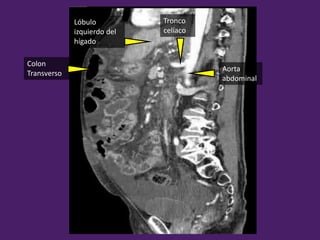

Colon

Transverso

Tronco

celíaco

Lóbulo

izquierdo del

hígado

Aorta

abdominal

Arteria

mesentérica

superior

Vena Renal

izquierda